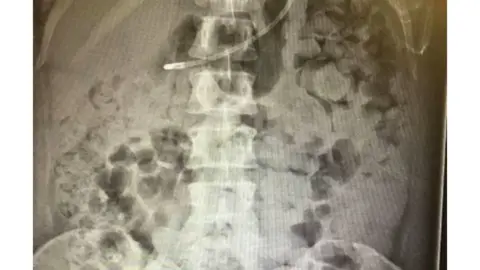

"They were able to remove all of the impacted and constipated stool," she said, adding it was a "massive relief".

NHS/Kelly YeomanMs Yeoman was initially admitted to St Michael's Hospital in August to check for endometriosis.

She was later treated at Southmead Hospital when complications developed following the previous surgery.